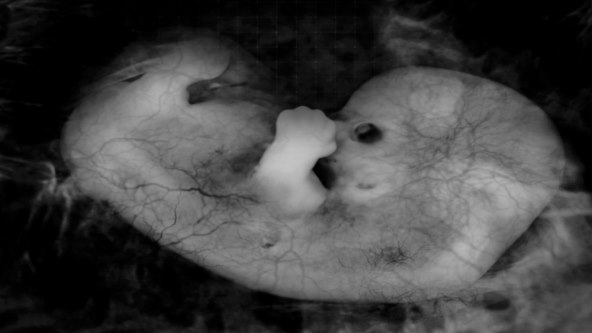

U kojoj je mjeri dijete u trbuhu već pravi mali čovjek, postaje jasno kada se promotre prijevremeno rođena djeca: bebama rođenim oko 25. tjedna trudnoće nedostaju samo zaštitno salo pod kožom i stabilni plućni mjehurići. Pogledate li njihova ganutljivo mudra lica, nećete se ni časka dvoumiti da ti mališani pokazuju čitavu paletu ljudskih osjećaja. Mršte čelo i cvile kada im se primjerice mora uzeti krv; opuštaju se i ponekad se čak i smješkaju ako smiju ležati na majčinim golim grudima i slušati otkucaje njezina srca.

Najprije se budi osjet opipa: koža reagira već u sedmom tjednu. Dijete može osjetiti kako je okruženo plodnom vodom, njegov organizam osjeća ritam majčinih unutarnjih organa, njiše se s otkucajima njezina srca.